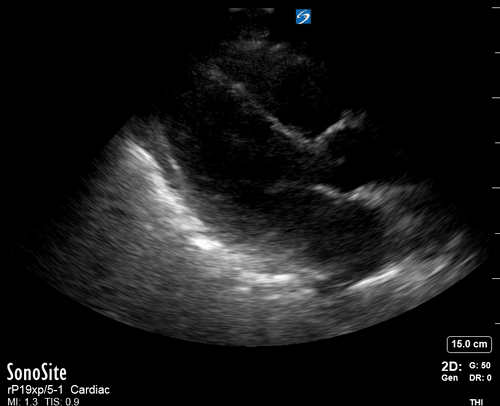

THE VIEWS

The A4C view provides an accurate chamber size comparison. However, achieving a proper A4C view (avoiding foreshortening or ballooning, and visualising the four chambers with a vertically oriented interventricular septum) can be a challenging exercise of image acquisition. Additionally, the PSAX view at the level of the papillary muscles shows both LV and RV side by side and is useful to assess function and size. When RV pressure is high, the septum will be pushed and flattened towards the LV, resulting in the characteristic “D-shaped” LV or “D sign”.

PITFALLS

When comparing size, beware of correct image acquisition, as oblique planes lead to misinterpreting the RV:LV ratio. For apical views be sure to slide the probe sufficiently laterally on the chest wall so that it lies over the true apex. Also, be sure to obtain a real horizontal plane, avoiding foreshortening (ballooning). For the PLAX view it is useful to fan through the heart’s long axis, making sure that LV visualization is maximized relative to the RV. Furthermore, an understanding of probe placement and marker orientation conventions is fundamental. If inadvertently scanning in reverse orientation, the normally larger LV could be mistaken for an abnormally enlarged RV.